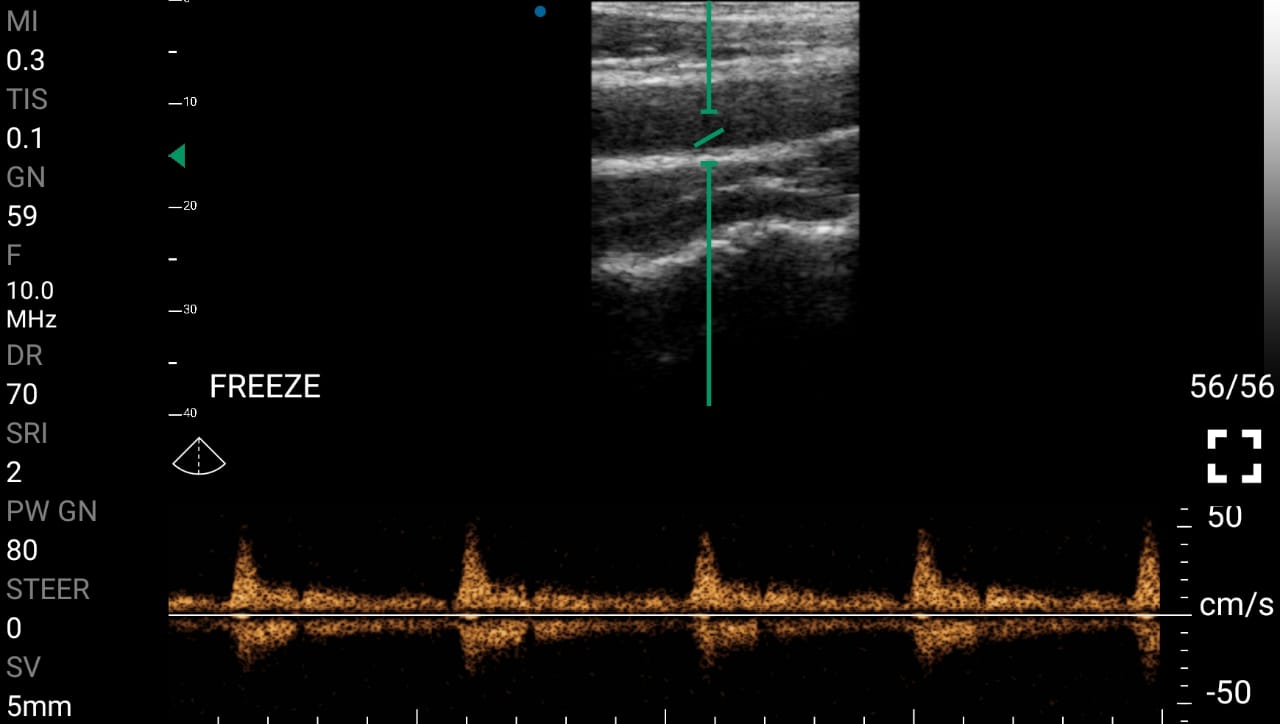

• Αξιολόγηση της ροής του αίματος: Η υπερηχογραφία Doppler παρέχει άμεσες πληροφορίες για τη ροή του αίματος σε διάφορες περιοχές του σώματος, προσδιορίζοντας τις περιοχές που χρήζουν επεμβατικής αποκατάστασης.

Παραδείγματα

Ολες οι παραπάνω απεικονιστικές εξετάσεις έχουν ληφθεί από φορητή συσκευή όπως: Apple Iphone, Tablet, Samsung Mobile Phones και διάφορες άλλες φορητές συσκευές.